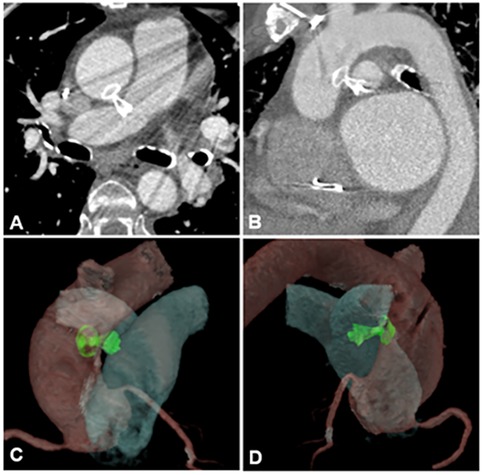

Further investigation with transesophageal echocardiography (TEE) confirmed the presence of the fistula, which measured 2 mm at the aortic orifice (Figures 1A,B and Supplementary Videos S1, S2), located approximately 30 mm above the aortic valve plane. In the midesophageal long-axis view of the ascending aorta, the maximum pressure gradient across the fistula was 78 mmHg. This resulted in high pulmonary output, with an estimated pulmonary artery systolic pressure of 44 mmHg.

Figure 1

Imaging methods utilized for aortopulmonary fistula diagnosis. (A) TEE midesophagus ascending aorta short-axis section. (B) Midesophageal long-axis section. (C) Angiotomography of aortic and pulmonary vessels. (D) 3D angiotomography reconstruction. APF, aortopulmonary fistula; AA, ascending aorta; MPA, main pulmonary artery; LPA, left pulmonary artery; RPA, right pulmonary artery; LMCA, left main coronary artery; RCA, right coronary artery; RV, right ventricle; LV, left ventricle.

Subsequently, computed tomography angiography (CTA) with 3D reconstruction of the aortic and pulmonary vessels was performed to determine the optimal correction strategy and assess the distance between the fistula and the coronary arteries (Figures 1C,D and Supplementary Videos S3). CTA revealed an aortopulmonary fistula located 26 mm above the aortic root and 38 mm below the brachiocephalic artery. The fistulous tract measured 10 mm in length, with an aortic orifice measuring 3 × 2 mm and a pulmonary orifice measuring 6 × 2 mm.